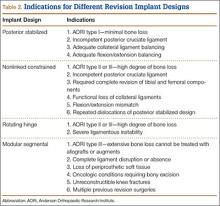

In this article, we review the classification systems used for revision TKA as well as the types of prosthetic designs that can be used: posterior stabilized, nonlinked constrained, rotating hinge, and modular segmental.

In addition to understanding bone loss in revision TKA, surgeons must be aware of soft-tissue deficiencies (eg, collateral ligaments, extensor mechanism), which also influence type and amount of prosthesis constraint. Specifically, constraint choice depends on amount of bone loss and on the condition of stabilizing tissues, such as the collateral ligaments. Under conditions of minimal bone loss and intact peripheral ligaments, a less constrained device, such as a primary posterior stabilized system, can be considered. When ligaments are present but insufficient, a semiconstrained device is recommended. In the presence of medial collateral ligament attenuation or complete medial or lateral collateral ligament dysfunction, a fully constrained prosthesis is required.8 Therefore, amount of bone loss or soft-tissue deficiency often dictates which prosthesis to use.

However, studies have shown that posterior stabilized TKAs have a limited role in revision TKAs, as the amount of ligamentous and bony damage is often underestimated in these patients, and use of a primary implant in a revision setting often requires additional augments, all of which may have contributed to the high failure rate. Thus, this design should be used only when the patient has adequate bone stock (AORI type I) and collateral ligament tension. This situation further emphasizes the importance of performing intraoperative testing for ligamentous balance and bone deficit evaluation in order to determine the most appropriate implant (Table 2).